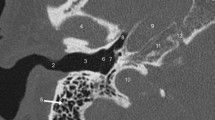

Probably the most important function of the CT evaluation is to detect contraindications for the cochlear implantation including cochlear aplasia but also aplasia of the cochlear nerve canal/cochlear aperture (Fig. 7.1).

The atresia of the cochlear aperture is a strong indicator of underlying cochlear nerve anomaly [23, 24]. Tahir et al. reported that all 21 cases with cochlear aperture atresia in their series had accompanying cochlear nerve deficiency (either aplasia or hypoplasia) [23]. The dimension of a patent cochlear aperture thus needs to be assessed, as its diameter is a marker of the cochlear nerve status [23, 25]. The cochlear aperture is considered stenotic when it is narrower than 1.4 mm (Fig. 7.2) [7, 26,27,28,29]. It is critical to realize that the aperture can be stenotic in the presence of a normal-appearing and normal-sized cochlea; thus, a normal cochlear shape does not always indicate normal cochlear nerve structure and further imaging with MR is required to assess the cochlear nerve status [23]. The internal auditory canal size is also crucial for the preoperative assessment.

The IAC is considered stenotic when the diameter at its midpoint is smaller than 2 mm [30]. The IAC stenosis or atresia may easily be demonstrated by CT and the finding of a narrow or aplastic IAC again should raise concern for a deficiency of the cochlear nerve [24, 31]. However, the IAC morphology is an unreliable surrogate marker of CN integrity and as reported by Adunka et al., a normal IAC diameter can be seen in up to half of cochlear nerve aplasia patients [23, 32].

During the imaging evaluation, the cochlea should be carefully assessed not only for possible malformations as the type and severity of the cochlear anomaly will determine the type of the implant used, but also for possible presence of labyrinthine ossificans (Fig. 7.3). Furthermore, CT may demonstrate anomalies of the bony labyrinth such as Paget and otosclerosis (Fig. 7.4) that could increase the incidence of postimplant complications such as facial nerve irritation.